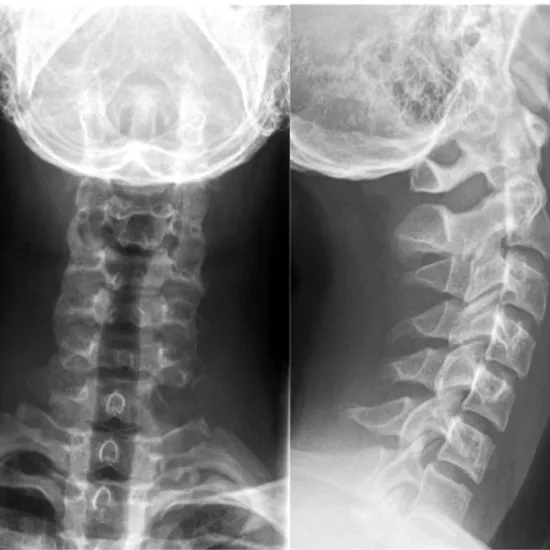

X-ray Cervical AP, Lat, Both Oblique

X-ray Cervical Spine AP, LAT, and both oblique tests to see the first seven vertebrae (C1–C7) of the spinal column (backbone) in the neck area. It also helps them see their intervertebral discs and the skin, muscles, and other soft tissues around them.